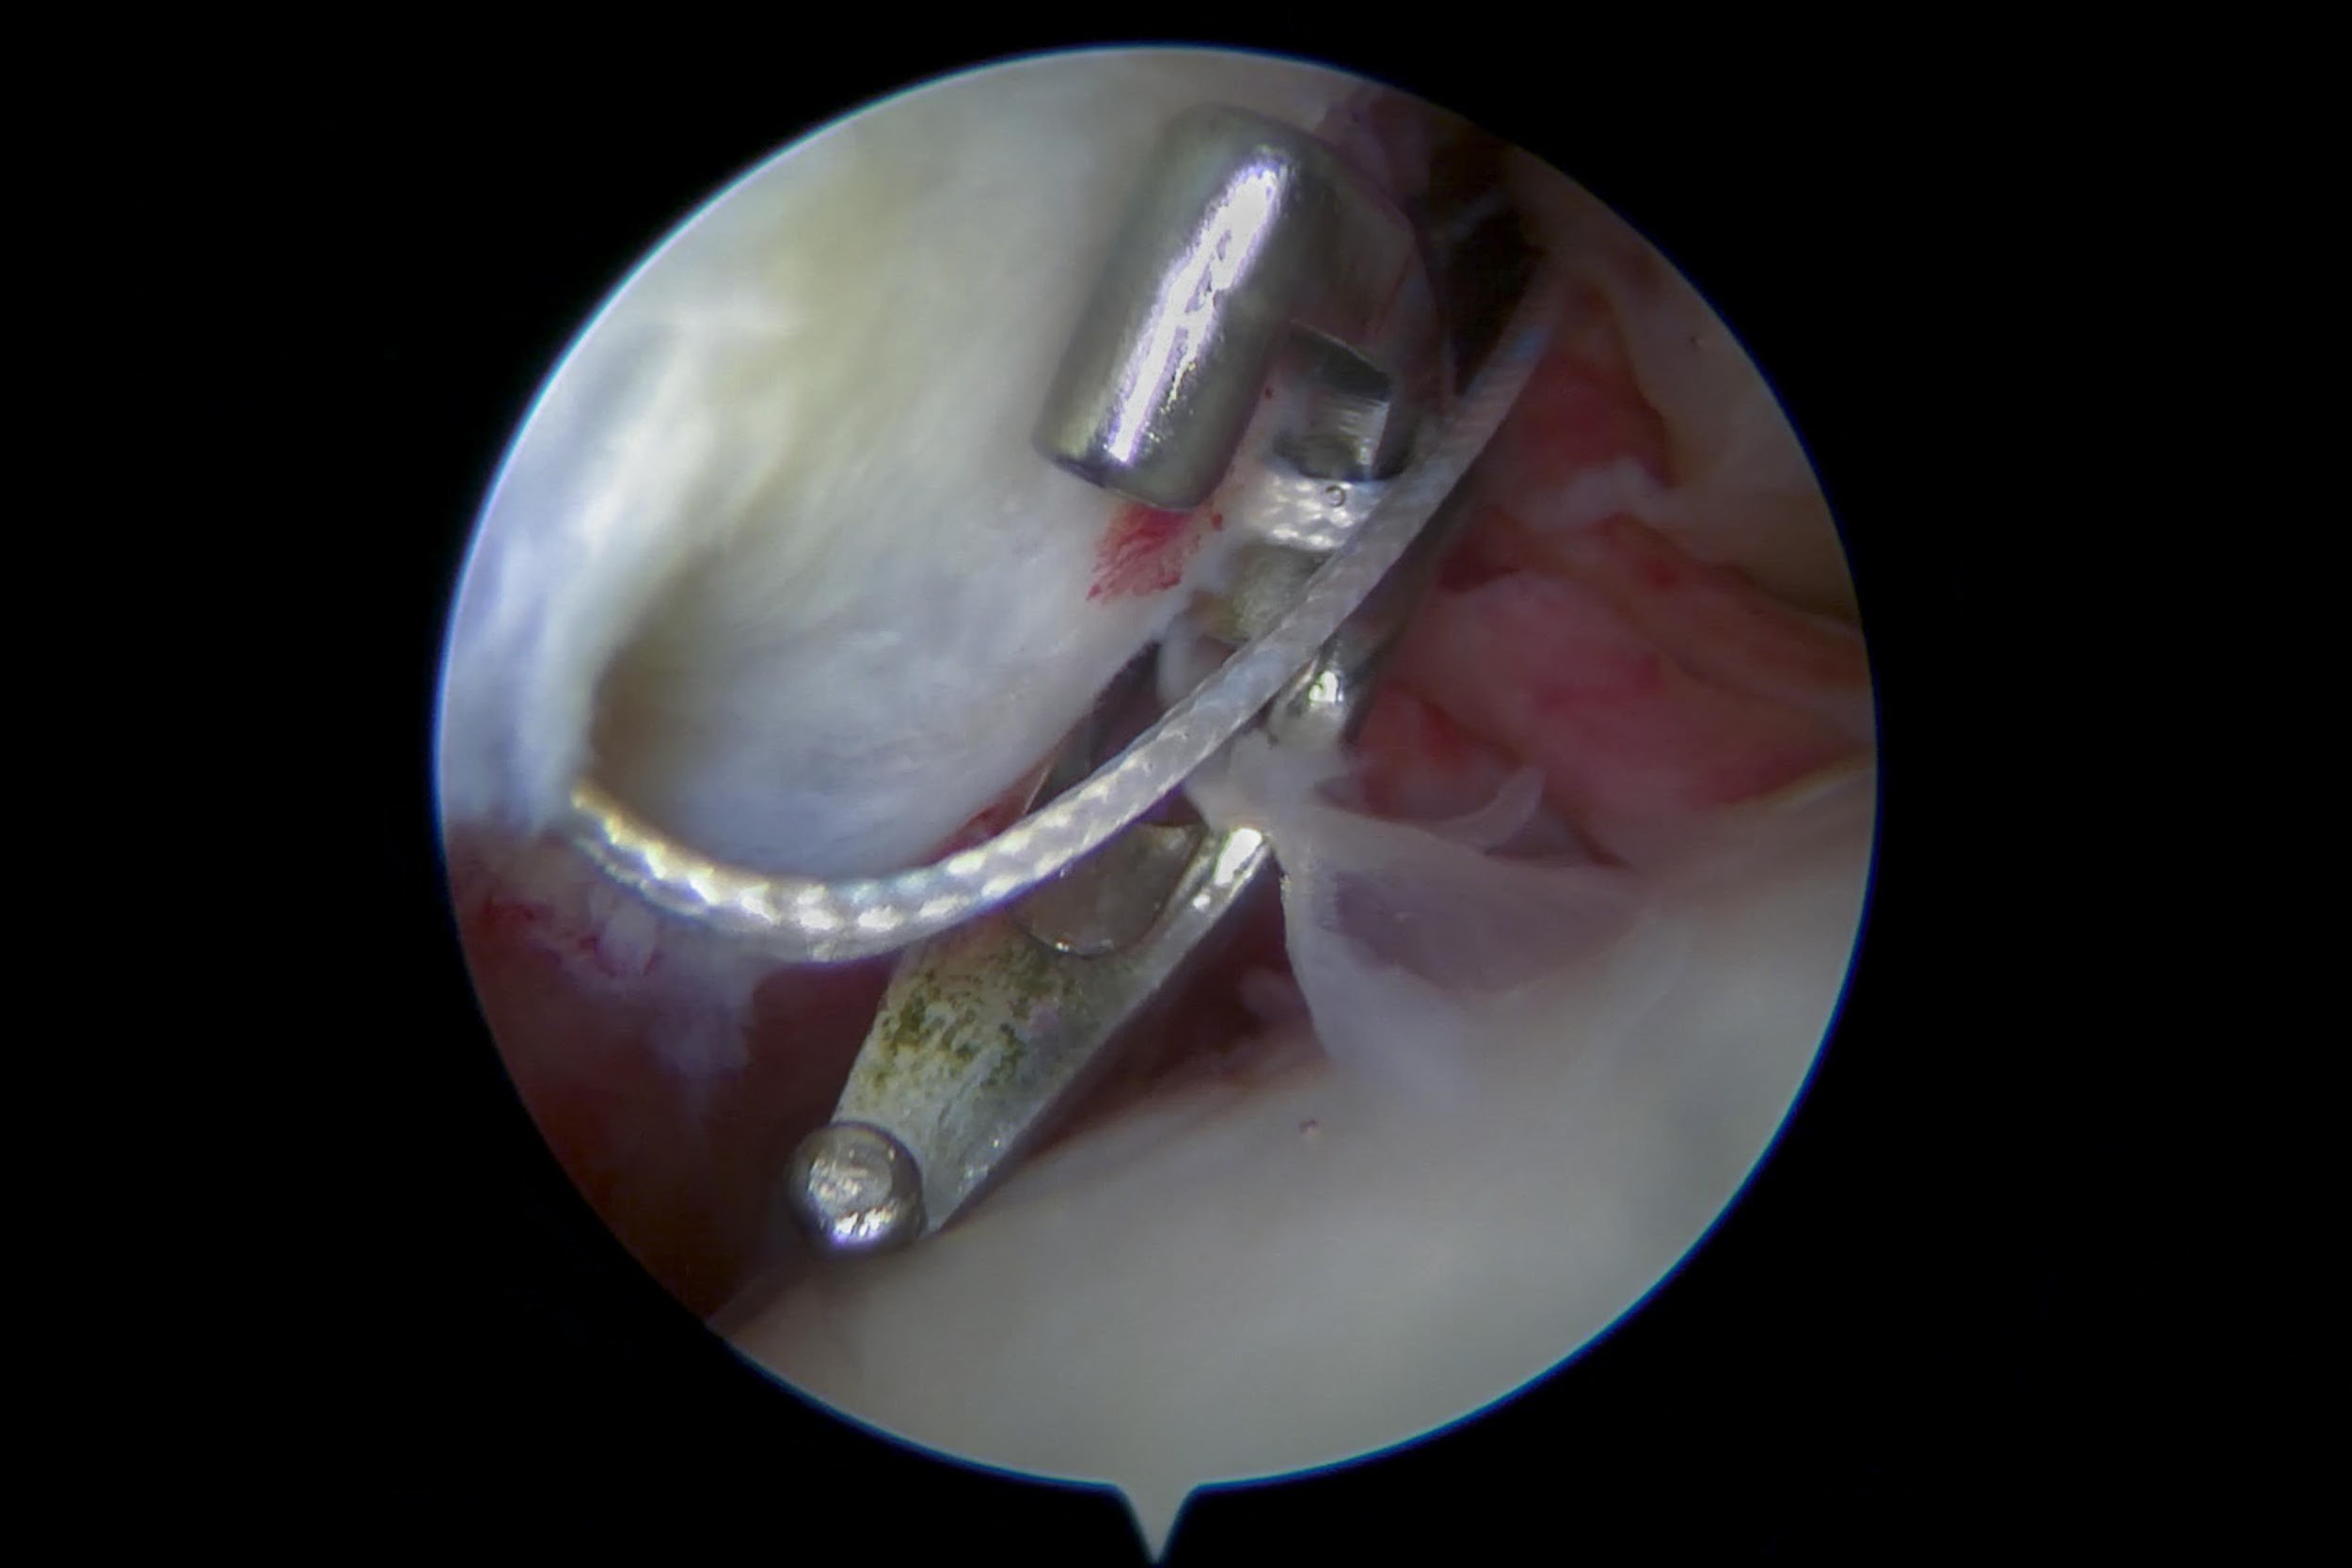

Arthroscopic Shoulder Surgery

If symptoms persist despite conservative treatment, minimally invasive arthroscopic surgery may be recommended.

Procedures include:

- SLAP repair

- Rotator cuff repair

- Capsular stabilization

- Debridement of damaged tissue